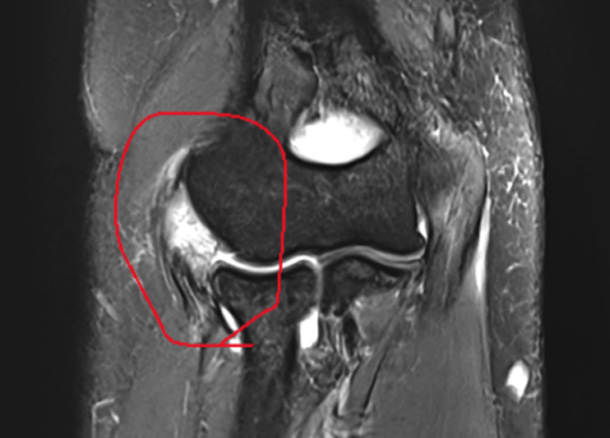

정확한 진단

& 치료 계획

X-Ray, 초음파, MRI 등 검사

신경조직 압박, 신경증상 등 파악

진단 증상에 따라 치료계획을 세웁니다.

Before 수술 전